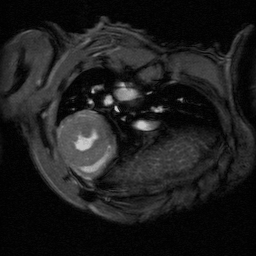

The ultra-high field of the BioSpec 152/11 provides extreme sensitivity for greatest resolution. Its streamlined design for mice studies makes handling simple, while its powerful software guarantees best results. It can be equipped with the MRI CryoProbe to increase sensitivity even further and together with the gradient strength of up to 1000 mT/m, highest resolution is achieved. It is built with nitrogen-free Ultra Shielded and helium Refrigerated (US/R) magnet technology for long service intervals

• Crisp and highly resolved images with native gradient strength of 740 mT/m, upgradable to 1000 mT/m

• MRI CryoProbe for exceptional increase in sensitivity